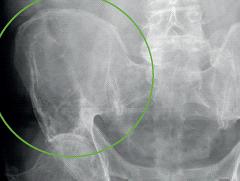

Een patiënt met een pijnlijke bothaard bij Kahler Lees meer over Een patiënt met een pijnlijke bothaard bij Kahler Een patiënt met een pijnlijke bothaard bij Kahler

De ziekte van Kahler is een kwaadaardige plasmacelaandoening van het beenmerg die gekenmerkt wordt door een overproductie van afweereiwitten (immunoglobulinen). Klinisch kan deze ziekte zich onder andere presenteren met botpijnen of pathologische fracturen als gevolg van botaantasting. In dit artikel wordt de casus beschreven van een patiënt met een bothaard op een röntgenfoto als gevolg van de ziekte van Kahler. De achtergrond van de ziekte en specifieke bevindingen die gevonden kunnen worden bij het aanvullend onderzoek worden uiteengezet.